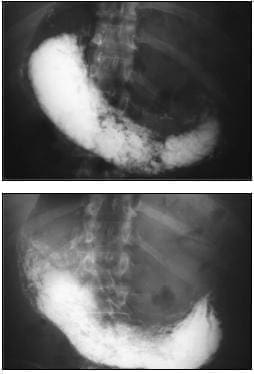

Por lo anterior, se decidió solicitar una tomografía computadorizada de tórax (figura 2) que evidenció la distensión de la cámara gástrica con nivel hidroaéreo, sin paso del medio de contraste al intestino delgado o grueso, por lo que el Servicio de Radiología realizó inmediatamente un estudio de vías digestivas altas (figura 3) que concluyó la existencia de desviación de antro gástrico hacia la izquierda y sin paso del medio de contraste al resto de las asas intestinales.

FIGURA 2. Tomografía computadorizada de tórax y abdomen

A. Ascenso de asas intestinales delgadas junto con grasa del mesenterio, que ocupan la región basal del hemitórax izquierdo en localización paracardiaca.

B. Estómago de localización central, distendido, con sonda nasogástrica en el interior y nivel hidroaéreo; no se obtuvo opacidad de las asas intestinales delgadas ni del intestino grueso.

FIGURA 3. Vías digestivas altas. Adecuado paso del medio de contraste a través del esófago, sin presencia de hernia hiatal, cámara gástrica distendida y retraso en el vaciamiento gástrico, con desviación hacia la izquierda del antro pilórico; éste se controla, aproximadamente, una hora después, sin que se observe paso del medio de contraste hacia el duodeno. Se consideró como diagnóstico un síndrome pilórico.